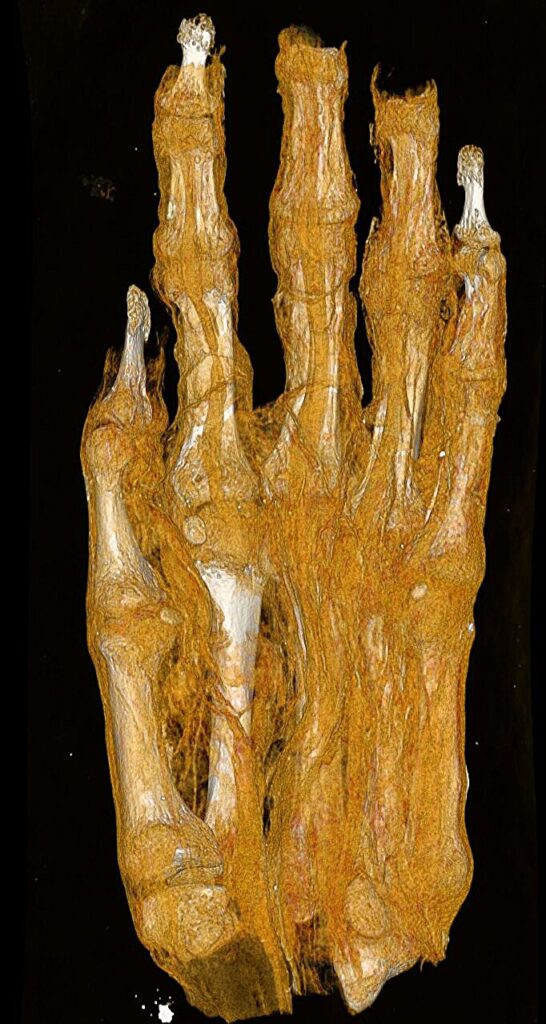

这项新成像项目最引人注目的方面之一是能够纠正长期存在的历史误认。在考古学的世界里,事情并不总是表面看起来的那样。其中一组遗骸被送入博物馆,仅被认定为“木乃伊包裹”。由于没有内部成像,最初被归类为人头。后来,有人推测它可能是鸟的木乃伊。

直到CT技术的帮助,真相才浮出水面:包裹里实际上是一只木乃伊化的成年脚。新的高分辨率扫描现在更进一步,分析包裹在肢体上的绷带的不同层次。图像清晰显示纺织残片中不同的结构特征,可能为具体木乃伊制作技术及个体是否患有任何可识别疾病提供线索。虽然研究人员认为这只脚最初是完整木乃伊的一部分,但它被分离的原因以及解剖的时间仍然是团队仍在努力解开的谜团。